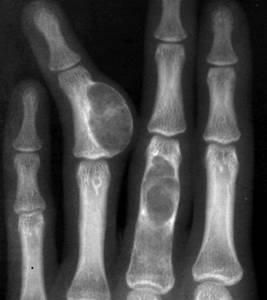

已往曾被命名為“成骨性纖維瘤”、“巨型骨樣骨瘤”等,病理性骨折

目前均已被廢棄。本病很少見。腫瘤的主要組織成分為血管豐富的骨樣組織,新生骨質以及大量骨母細胞。隨著腫瘤發展上述組織可相繼引起各種變化,因此難與骨巨細胞瘤及骨肉瘤鑑別。過去本病一直被認為屬良性腫瘤,近年有肺部轉移病例的報導,但其組織學檢查在此時仍無明顯惡變,面其生物行為可能發生惡變故認為有潛在惡性變可能。發病年齡多數在10~25歲之間,女多於男,發生部位以脊柱最多見,手足部次之,其他部位偶爾發生。起病緩慢。大多數患者僅感輕度疼痛。發生在脊柱者可有不同程度的脊髓或神經根壓迫症狀。X線表現可因腫瘤的鈣化或骨化程度而呈各種透明陰影,甚至密度增深陰影。一般腫瘤與周圍骨組織分界清晰,兩者之間常有明顯骨質硬化。在骨皮質時皮質常變薄並有一層骨膜新生骨。治療以手術抓刮植骨為主,病變在脊柱手術不能徹底可在減壓後加用放射治療。骨肉瘤

最為常見,有單發性與多發性。多發性多為遺傳性多發性骨疣,如合併肢體發育障礙而產生畸形稱遺傳性畸形性軟骨異常增殖症。腫瘤項端有軟骨帽,其生長活躍故有可能轉變為軟骨肉瘤。在手術切除時必須將軟骨帽切除,以免復發或惡變。軟骨母細胞瘤

多見於青少年管狀骨,以肱骨上端為好發部位,手術刮除後可復發但惡變較少見。軟骨粘液纖維瘤